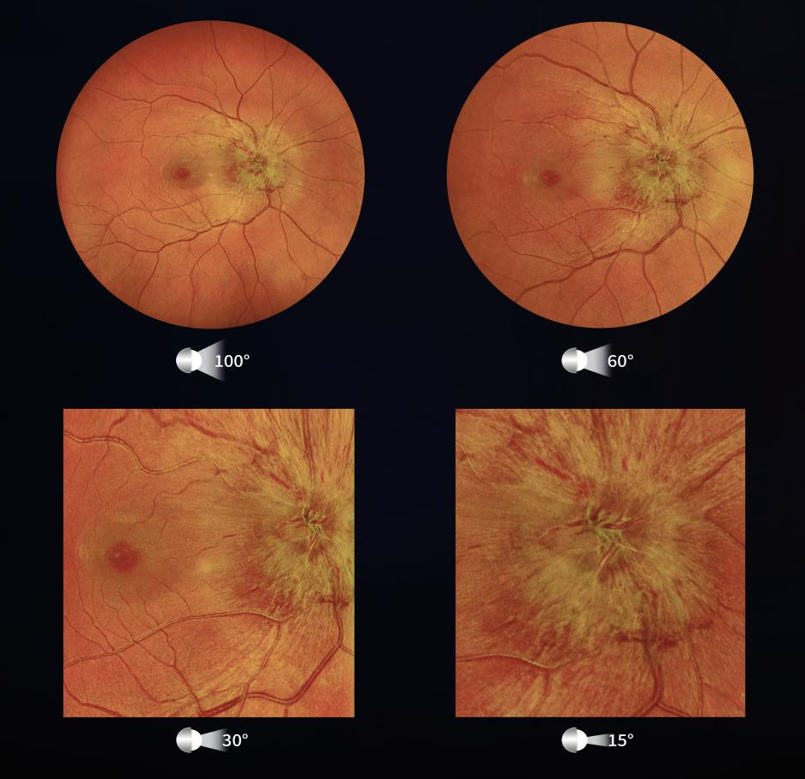

1、超广角

眼底位于眼球深处,常规的眼底照相检查仅能观测到眼底中心45°左右的有限区域。而许多眼底疾病的病变悄然发生在眼底周边的地区,仅凭借中心45°的眼底图像,眼底病变的潜在风险无法发现,许多患者很有可能因此错过治疗的黄金时间。超广角共焦激光眼底照相造影机,通过单张成像可扫描达150°超广角眼底范围,所具备的眼位引导功能,最大可捕捉到锯齿缘的眼底图像,能帮助医生看到更大范围、更多的眼底病信息,有利于眼科疾病的早期诊断,避免漏诊、误诊。